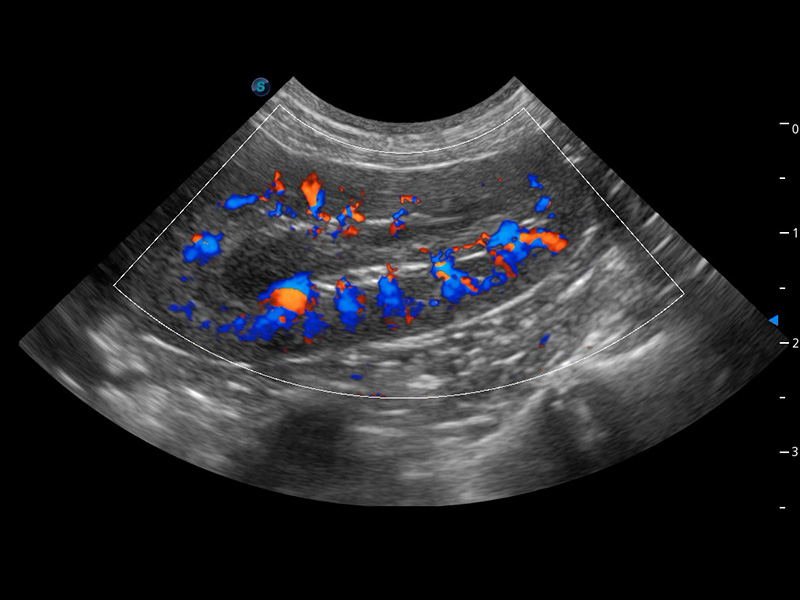

ProPet 60 作为一款高端台式动物超声设备,为动物医生的日常诊断提供了一系列贴合动物临床需求、解决临床实际问题的高级成像功能。凭借全系列高清探头,满足医生对腹部、心脏、生殖、浅表、肌骨等成像的所有需求,切实帮助您提升检查效率,提高诊断信心。

动物是人类最亲密的朋友和最值得信赖的伙伴。狗万官方网站也一直致力于探索动物专用的超声影像解决方案。 全新推出的ProPet系列,是狗万官方网站在动物超声影像智能化、专业化、精准化的一次跨越式革新。动物不能用言语来表述自己的不适,通过超声影像,ProPet系列搭建了动物医生与不同物种沟通的“桥梁”,为动物医生注入了“治愈之力”。